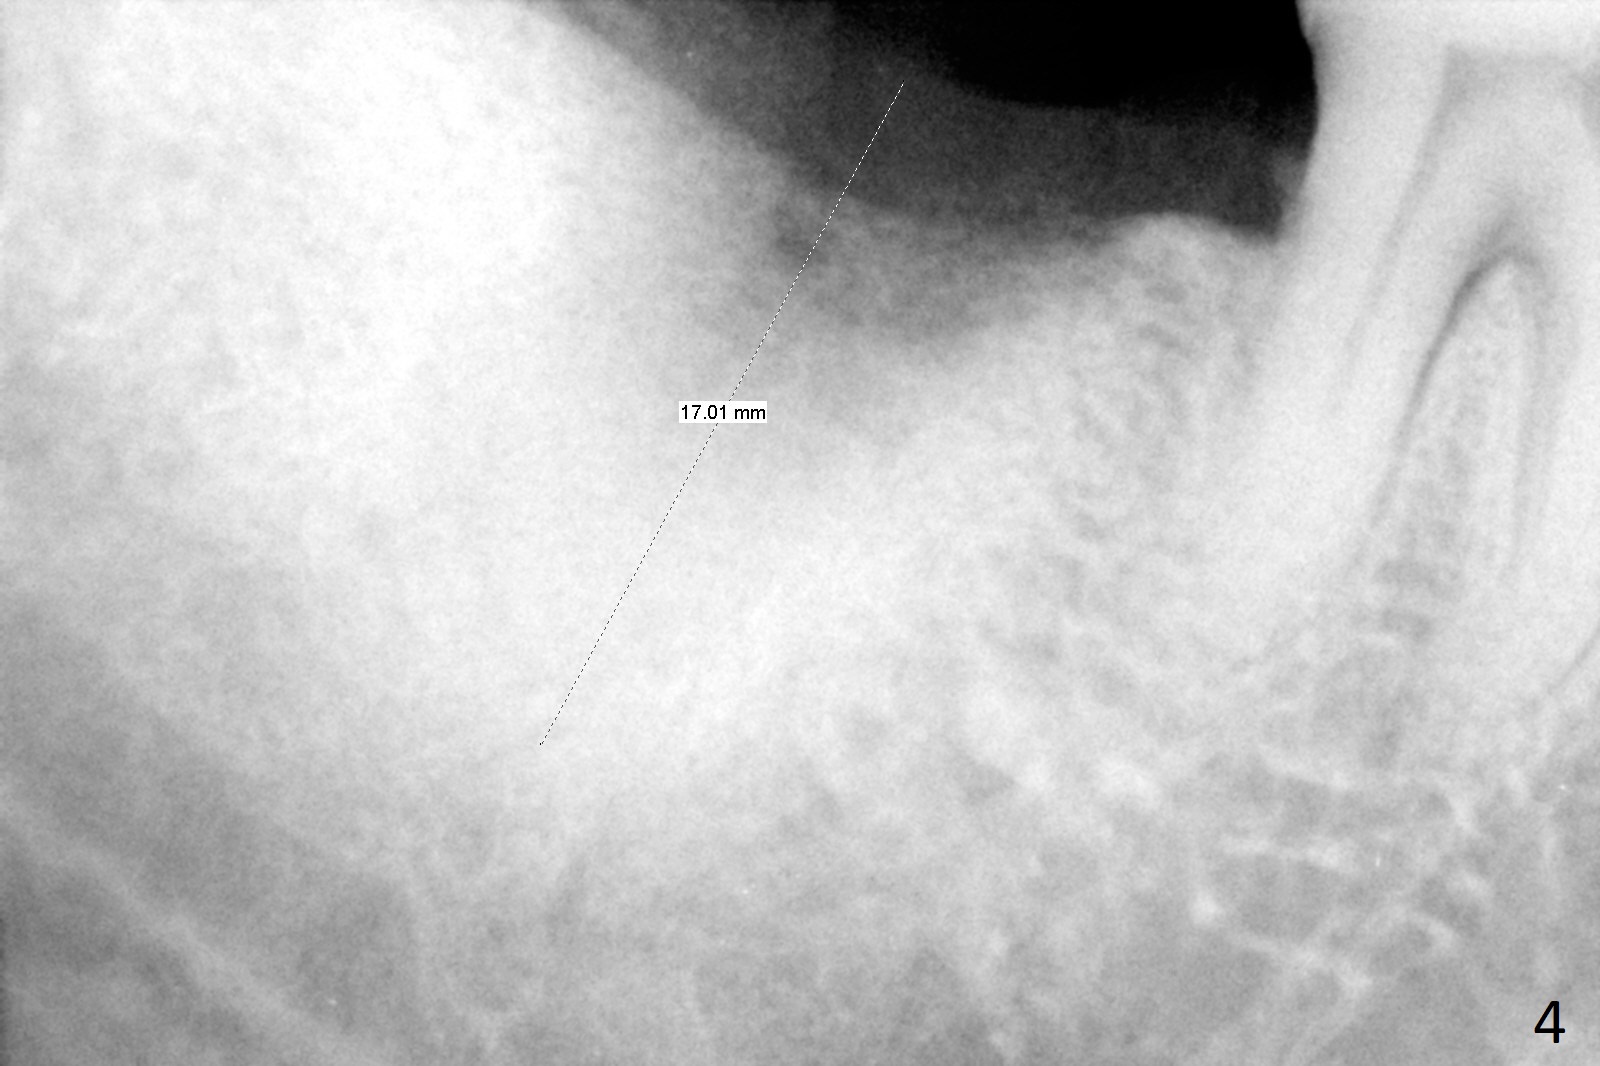

A 50-year-old man, a smoker, presents to clinic with pain of the tooth #15 with apparently occlusal trauma (Fig.1). Two years and three months after #15 extraction, he returns for #31 extraction (Fig.2) and socket preservation (Fig.3). The socket depth is 17 mm along the long axis of the socket 2.5 months post extraction (Fig.4, gingival level). Initial osteotomy is created in the mesial slope of the socket for 14 mm (Fig.5). After sequential osteotomy, a 6x17 mm tap is seated shallower (Fig.6) than the 2 mm drill (Fig.5). Following further osteotomy, a 7x14 mm implant is seated incompletely (Fig.7), which was not found intraop. The implant becomes loose with purulent discharge 19 days postop. The patient returns for 2nd placement 2 months post implant removal (Fig.8). Osteotomy is created probably in the mesial slope with 17 mm (bone level, Fig.9). After insertion of 5 (Fig.10) and 6 (Fig.11) x20 mm taps (tissue level), a 6x20 mm tissue-level implant is placed with clearance from the Inferior Alveolar Canal (Fig.12 yellow dashed line). The implant is restored 8.5 months postop (Fig.13) without bonding 5 mm 0 degree unipost. The crown dislodges 4 months post permanent cementation. Still the patient complains of small crown without occlusal contact. Impression is taken for a new normal-sized crown. The new crown becomes loose 1 year 9 months post cementation (Fig.14). The teeth #14 and 15 remain unrestored.